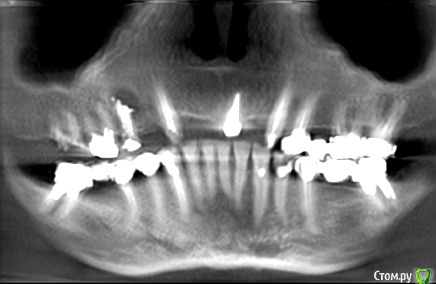

NazranDantist Опубликовано 8 мая, 2015 Поделиться Опубликовано 8 мая, 2015 Здравствуйте. Помогите с планом лечения. Планируется, вверх убрать все, кроме 13, 23, 24. Установка имплантов в области 12, 14, 16,17, 22, 25, 27. Дальше несъемная ортопедическая конструкция (еще определяемся). Низ - убрать 7-ки, импланты в области 6,7 с обеих сторон.Больше всего интересует этапность хирургических манипуляций. Как бы вы разбили здесь этапы, какие операции и в какой последовательности сделали бы?Взялись бы вверх одномоментно все убрать и закрутить? С низом вроде попроще. Кости очень много, гайморова пазуха знала, что будут ставить импланты П.С.: Я ортопед, но хочу освоить имплантацию, вот первая большая хирургическая работа, не знаю с какого края подойти Ссылка на комментарий

Аслан Опубликовано 9 мая, 2015 Поделиться Опубликовано 9 мая, 2015 с ушиванием... хм... самый просто вариант для Вас - засыпать в лунки стружку покрупнее но не тромбовать сильно, накрыть мембраной, края десны не сводить в плотную, чтобы не сильно уменьшать зону прикрепленной десны. можно и мембрану и формирователи если что. а можно и формирователи и без мембраны.Ваш снимок не самый информативный, но даже по нему острой необходимости сохрарнения клыков я не вижу. учтите в ортопедическом протоколе. если клыки останутся свои и будут маленькие мостики - восстановите клыковое ведение, если клыки будут удаляться и восстанавливаться в дуге на винтах - выводите групповое ведение с премолярами. а вот решение "подключить" клыки в подкове на имплантах - желаю Вам удачи в этом начинании. может Вы знаете что-то что позволяет объединить зубы и винты, но никто из ранее зарегестрированных на форуме такого не знает. 1 Ссылка на комментарий